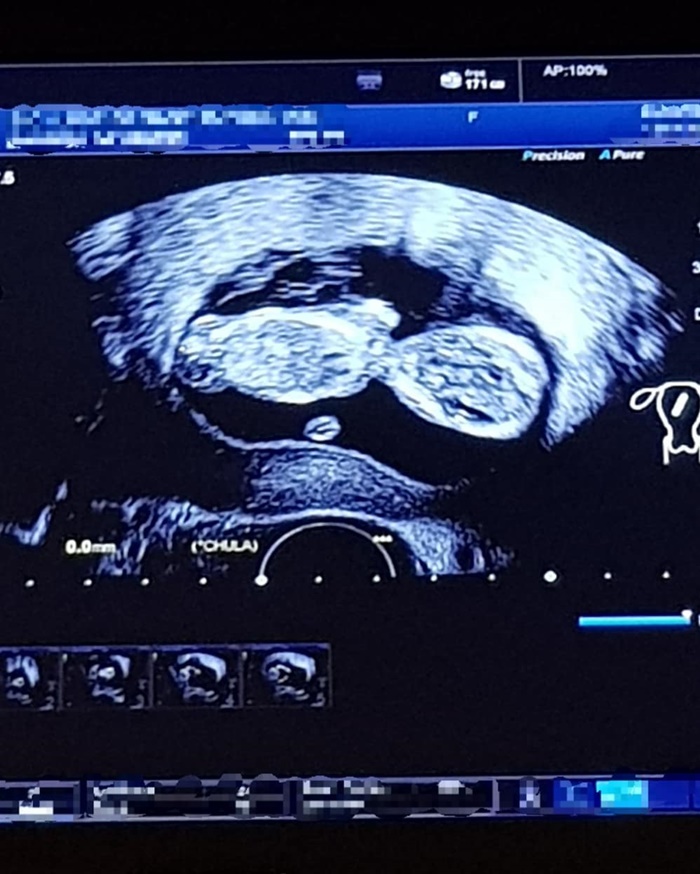

โดยสาวแนนซี่ นันทพร ได้เผยภาพถ่ายอัลตราซาวด์ลูกน้อยลง IG พร้อมข้อความว่า "When you just can’t hide it anymore and now it’s completed the first trimester. Can’t wait to see u my baby #ต่อไปนี้ไม่ทักกันว่าอ้วนขึ้นแล้วนะคะ #12weekspregnant"